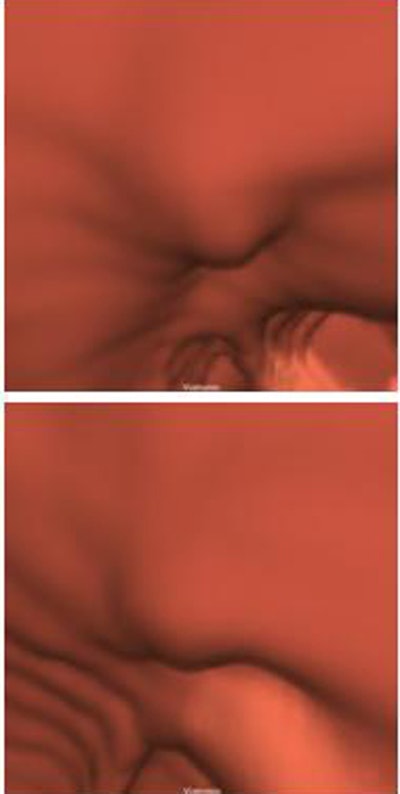

| Above, an adenoma measuring 8 mm at optical colonoscopy (per calibrated guidewire) measured 1.9 mm and 1.8 mm high and 7.7 mm and 7.0 mm wide in supine (top) and prone (bottom) CTC (per automated measurement algorithm), respectively. Below, a hyperplastic polyp measuring 8 mm at optical colonoscopy measured 2.46 mm and 1.65 mm high and 9.89 mm and 10.32 mm wide in supine (top) and prone (bottom) CTC images, respectively. The automated polyp measurement scheme utilizes a pattern-recognition topographic height method similar to that of a terrain map. Polyp contours are depicted as curves. All images courtesy of Dr. Ronald Summers, Ph.D. |